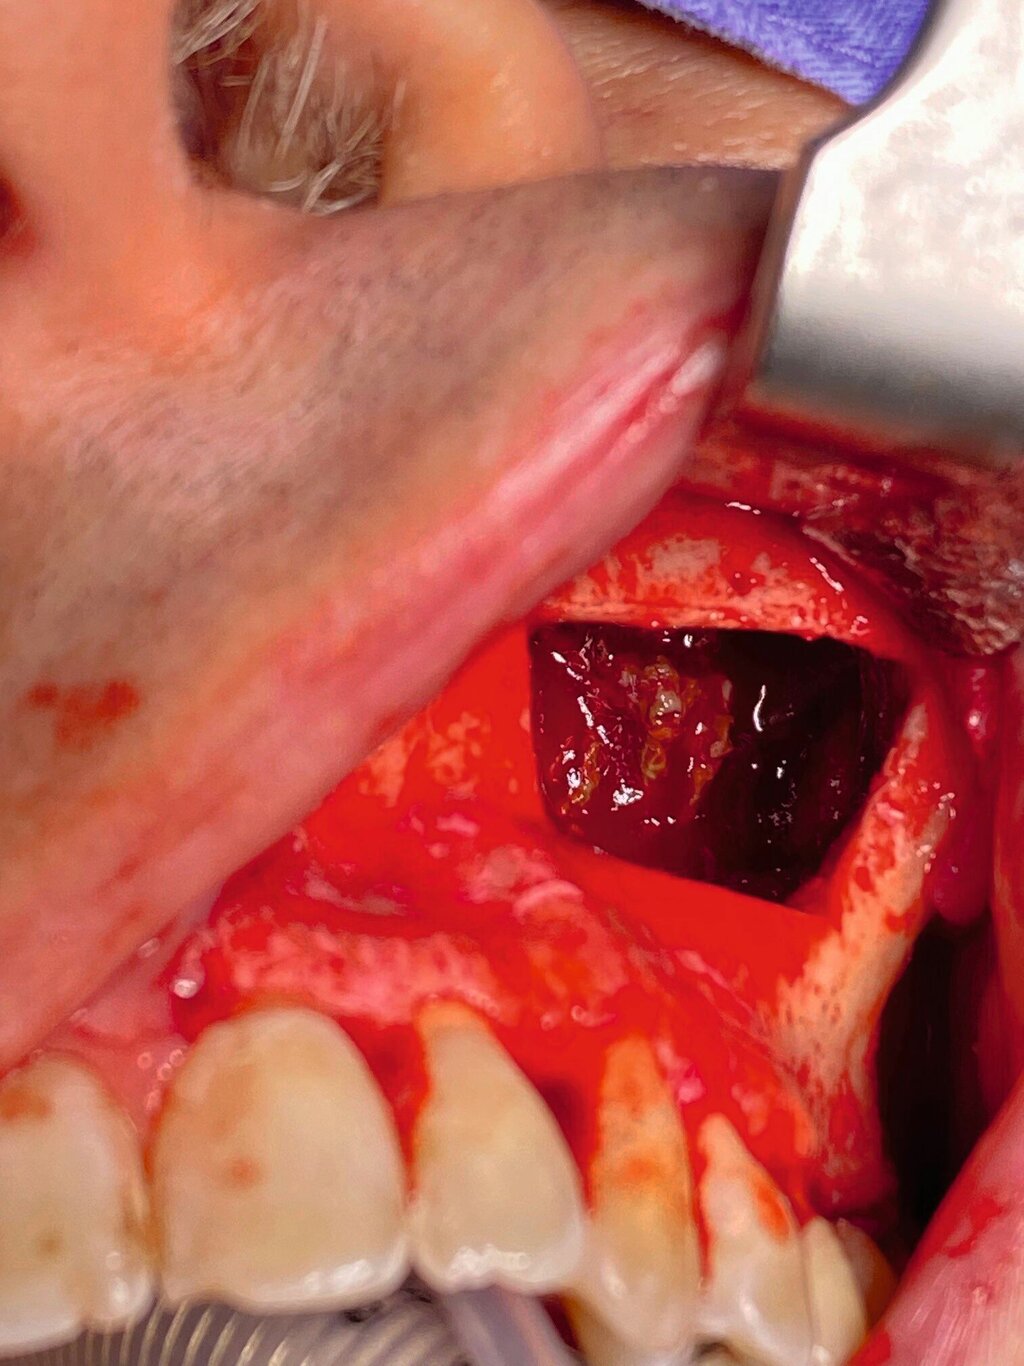

Die Therapie erfolgte in ambulanter Vollnarkose mittels Lindorf-Deckel-Technik. Nach marginaler Schnittführung und Darstellung der Kieferhöhlenvorderwand wurde mittels Piezosurgery ein knöcherner Deckel präpariert und der Sinus eröffnet (Abbildung 3). Es zeigten sich eine große Menge bröckeliges, schwarz verfärbtes Material sowie eine entzündlich veränderte Schleimhaut (Abbildung 4).

Die intraoperative Bergung braun-grauer bis grau-gelber und bröckeliger Weichgewebsmasse ist typisch für ein Aspergillom [Ciapuccini et al., 2017]. Der mikrobiologische Nachweis kann mittels Anzucht aus dem intraoperativ gewonnenen Material erfolgen, jedoch ist ein Zwischenergebnis der Kultur erst nach frühestens 24 bis 48 Stunden zu erwarten [McGinnis et al., 1977]. In der histologischen Aufarbeitung zeigen sich charakteristisch verzweigte Hyphen [Khongkhunthian et Reichart, 2001]. Im vorliegenden Fall wurde mit dem für die histopathologische Aufarbeitung gewonnenen Material eine zusätzliche PCR-Diagnostik durchgeführt, die auf den Nachweis von A. fumigatus schließen ließ.